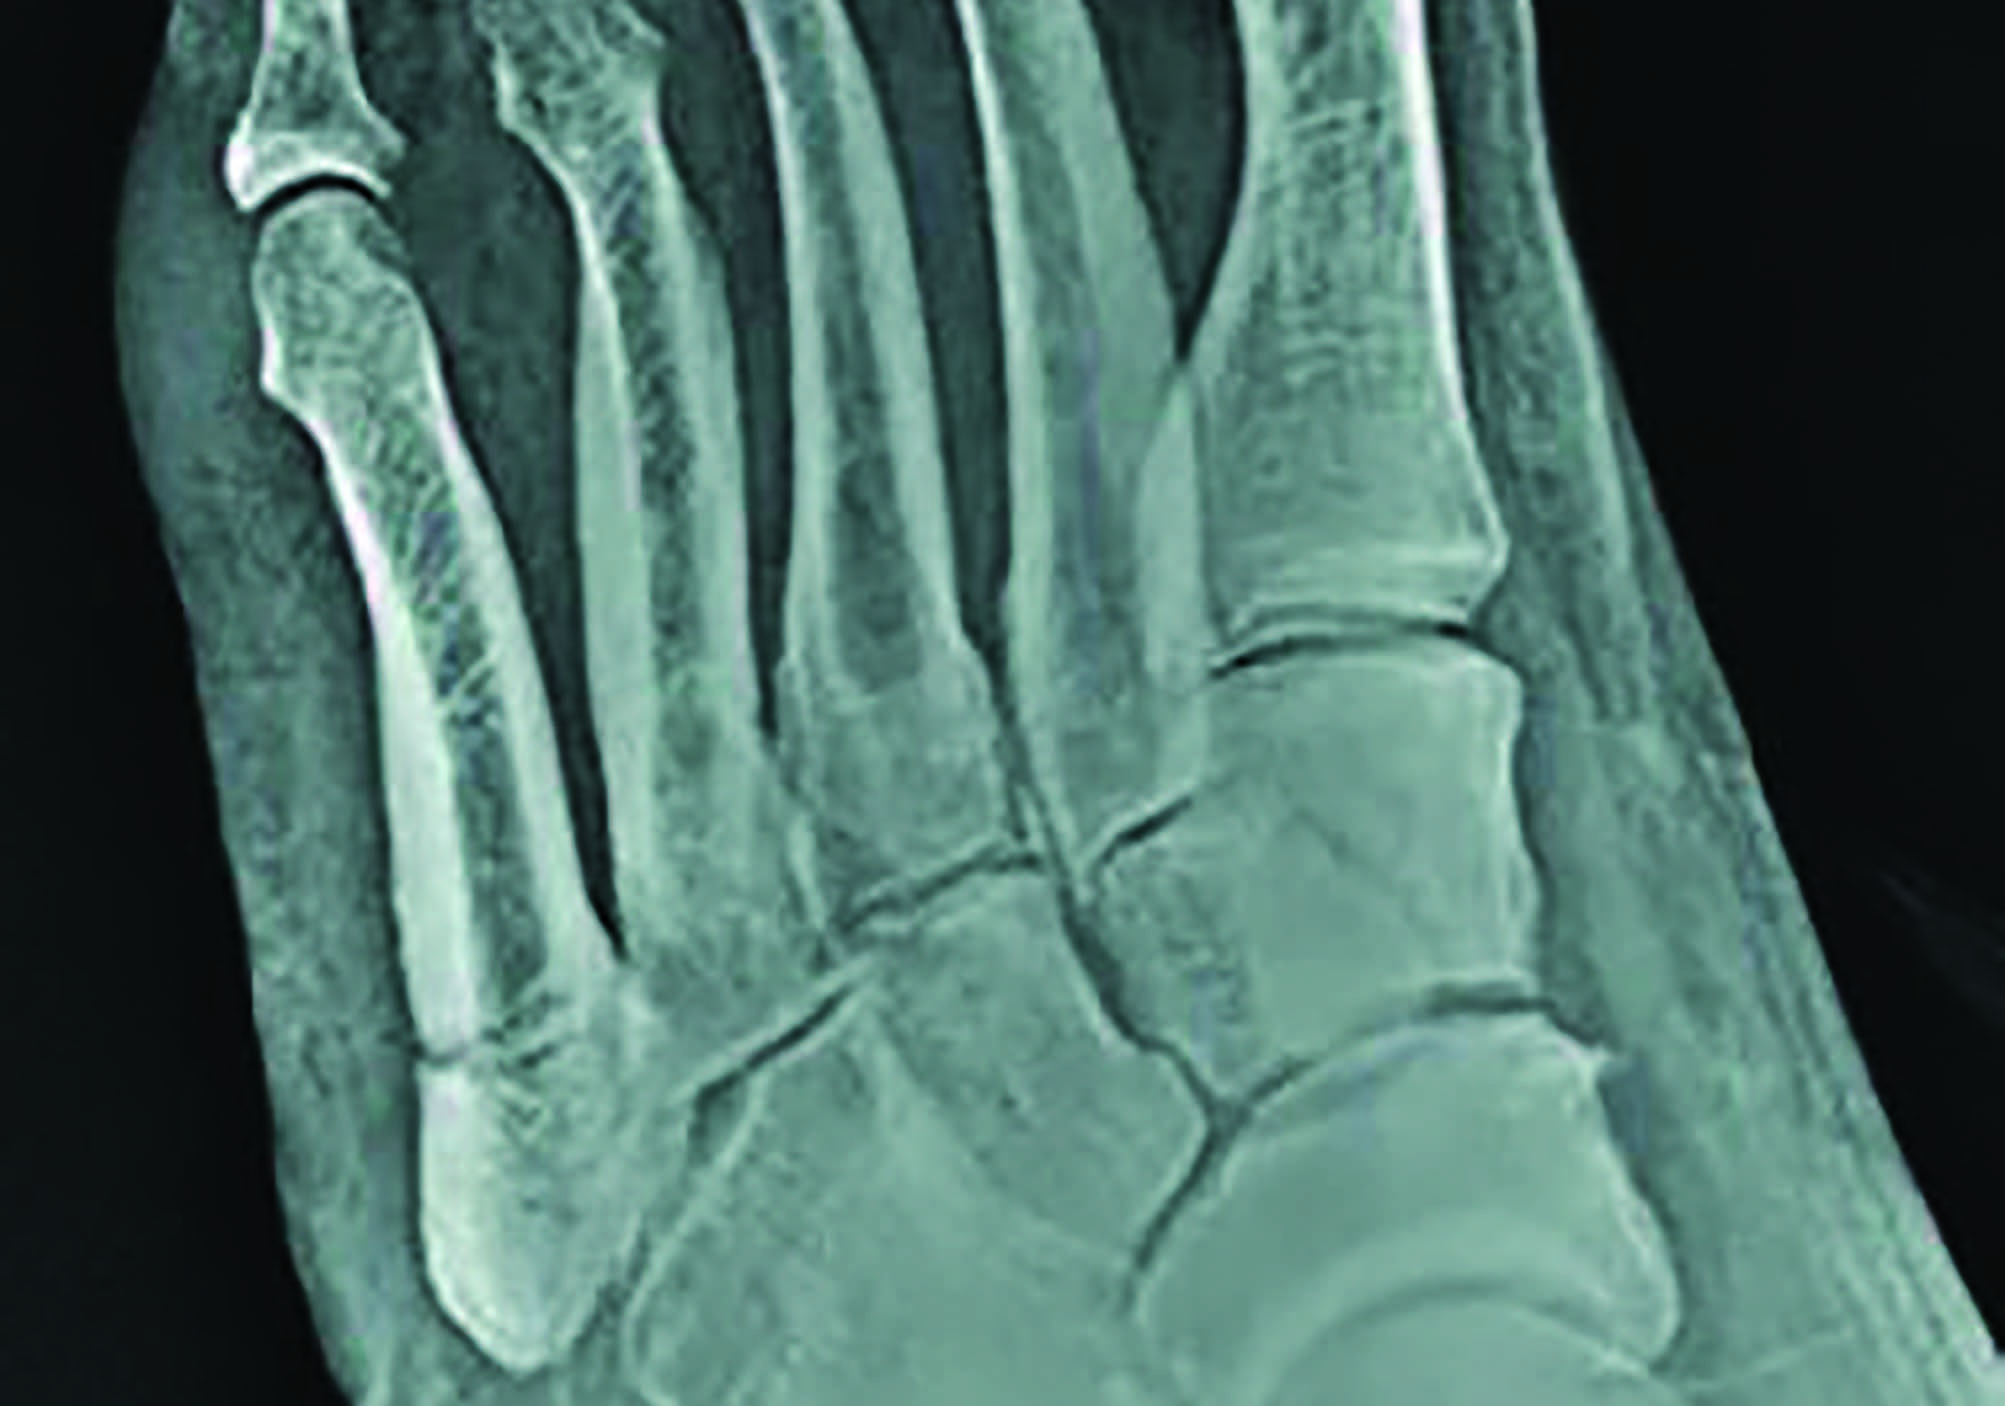

Authors of a recent study in Foot and Ankle International analyzed a database of 834 patients with proximal fifth metatarsal fractures to see if fracture zone (according to Lawrence and Botte’s classification) and weight-bearing status had an impact on time to fracture union in nonoperatively treated cases.

Of the fractures studied, 61.2 percent were zone 1, 18.8 percent zone 2, and 20.0 percent zone 3. Time to fracture union for zones 1, 2, and 3 was 7.5, 7.7, and 9.2 weeks, respectively. There was no time difference in fracture union between weight-bearing as tolerated and non-weight bearing pathways. Future surgery due to nonunion and/or delayed union occurred in 2.7, 3.2 and 3.8 percent of zone 1, 2, and 3 fractures, respectively. Refracture during the follow-up period occurred in 0.6 percent of zone 1 fractures and 8.9 percent of zone 3 fractures.

Kristine Hoffman, DPM, FACFAS says she typically treats zone 1 fractures conservatively and treating zone 2 and 3 fractures surgically in active and low-risk patients.

“Zone 1 injuries I typically treat weight-bearing as tolerated in a pneumatic walking boot,” he says. “This treatment algorithm is consistent across all patients and medical comorbidities. Zone 2 has a slightly higher operative management prevalence. I use the fourth tarsometatarsal articulation as my cutoff zone, as well as medical comorbidities, level of activity, and fracture pattern.”

He says that he manages an even higher rate of zone 3 fractures surgically, nearly always with intramedullary screw fixation.